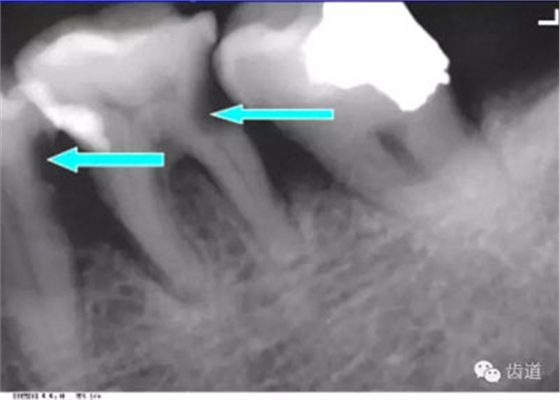

位于前磨牙根尖區(qū)域,為一大致圓形密度低的影像。頦孔位置變異大,多位于第二前磨牙根尖稍下,注意與根尖周病變區(qū)別,其要點(diǎn)是牙周膜及其骨硬板是否連續(xù)不斷。